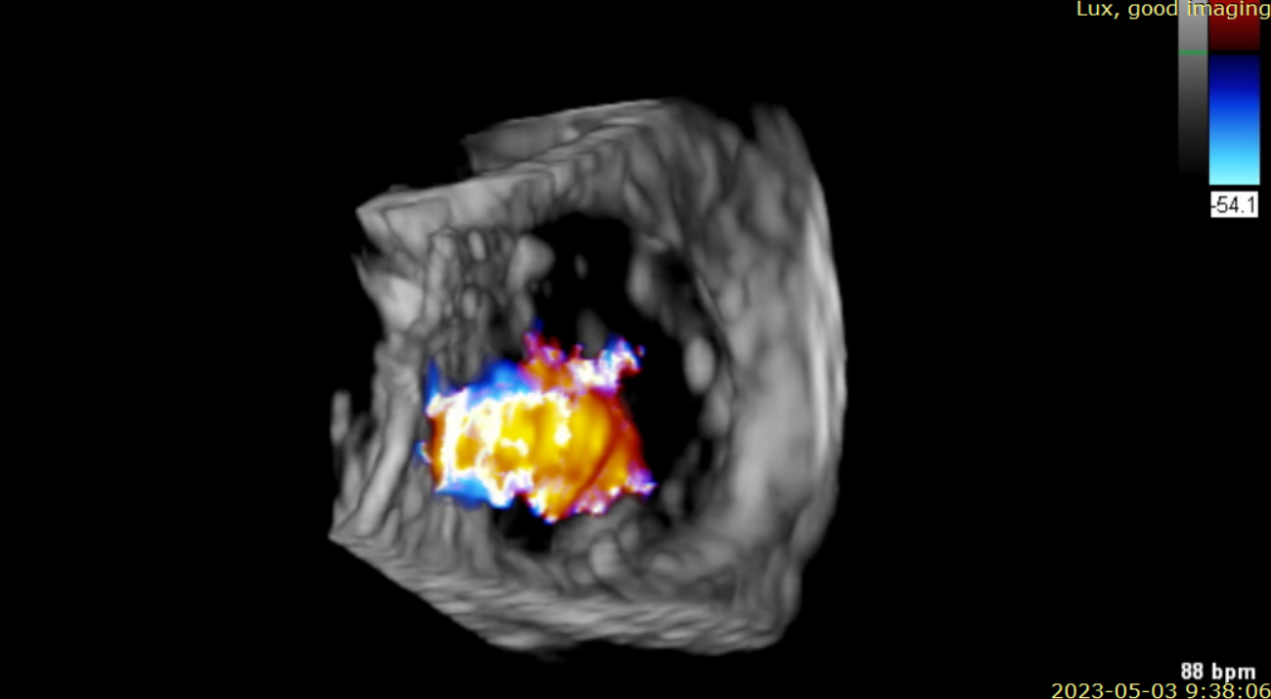

近日,美國紐約Montefiore醫(yī)學中心(Montrefiore Medical Center)的Azeem Latib教授團隊成功應(yīng)用LuX-Valve Plus經(jīng)血管三尖瓣置換系統(tǒng)為兩位三尖瓣大量反流的患者完成三尖瓣置換手術(shù)。術(shù)后超聲顯示人工三尖瓣植入穩(wěn)定,瓣葉啟閉良好,僅殘余微量瓣周漏?;颊哂谑中g(shù)室即刻拔除氣管插管,血流動力學改善顯著。此次手術(shù)是LuX-Valve Plus于紐約的首次臨床應(yīng)用,治療效果優(yōu)異。

術(shù)后Azeem Latib教授對LuX-Valve Plus經(jīng)血管三尖瓣置換系統(tǒng)的器械性能和治療效果大為稱贊,并且認為LuX-Valve Plus的手術(shù)體驗非常好。從治療效果來看,術(shù)后即刻超聲顯示三尖瓣反流幾乎完全消失,血流動力學改善顯著,患者恢復(fù)快。在面對復(fù)雜解剖結(jié)構(gòu)、超聲影像質(zhì)量不佳、有起搏導(dǎo)線干擾時,Lux-Valve Plus也體現(xiàn)了極強的適應(yīng)性。Thomas Modine教授參與了術(shù)中指導(dǎo),他同樣再次肯定了LuX-Valve Plus術(shù)中操作的便捷性,認為LuX-Valve Plus容錯率高,對術(shù)中影像的依賴小,并表達了后期希望可以更多地應(yīng)用LuX-Valve Plus三尖瓣置換系統(tǒng)于臨床實踐,讓更多的三尖瓣重度反流患者盡早獲益,改善預(yù)后。